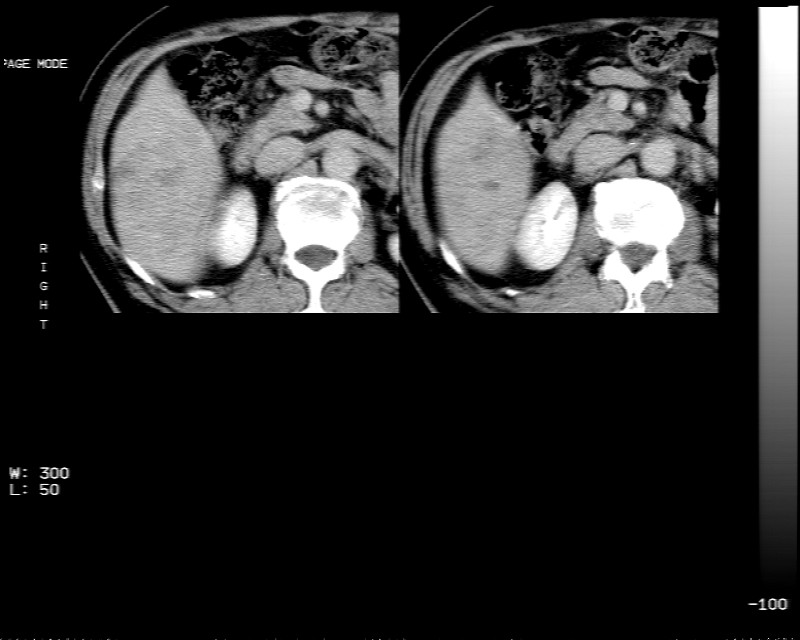

男 73岁 b超检肝右叶占位病变,afp阴性. 随访中.

肝右叶巨大占位性病变,平扫呈低密度改变,增强扫描动脉期病灶周围强化,门脉期强化未退出,延时期病灶周边强化与肝实质接近,病灶中心在各期均可见星状不强化区;首先考虑局灶性结节增生可能性大,其次为血管瘤。肝癌不能完全排外(不首先考虑肝癌是因为强化不支持快进快出特点)。

我看延迟期还不够,再延迟扫描排除血管瘤

平扫示:肝右后叶下段内见类圆形略低密度占位病灶,边界尚清楚,最大径约为102×71mm,ct值31~41hu。

动态增强扫描示:动脉期病灶显著不均性强化,病灶强化密度高于肝实质;平衡期病灶呈等密度;延迟扫描病灶密度略低于肝实质;三期均见占位病灶内有裂隙状无强化影。肝内胆管无扩张,腹膜后未见肿大淋巴结。

拟诊:肝右后叶下段内占位性病变,考虑为肝结节样增生。

建议进一步检查(mri/或穿刺活检),不排外肝ca。